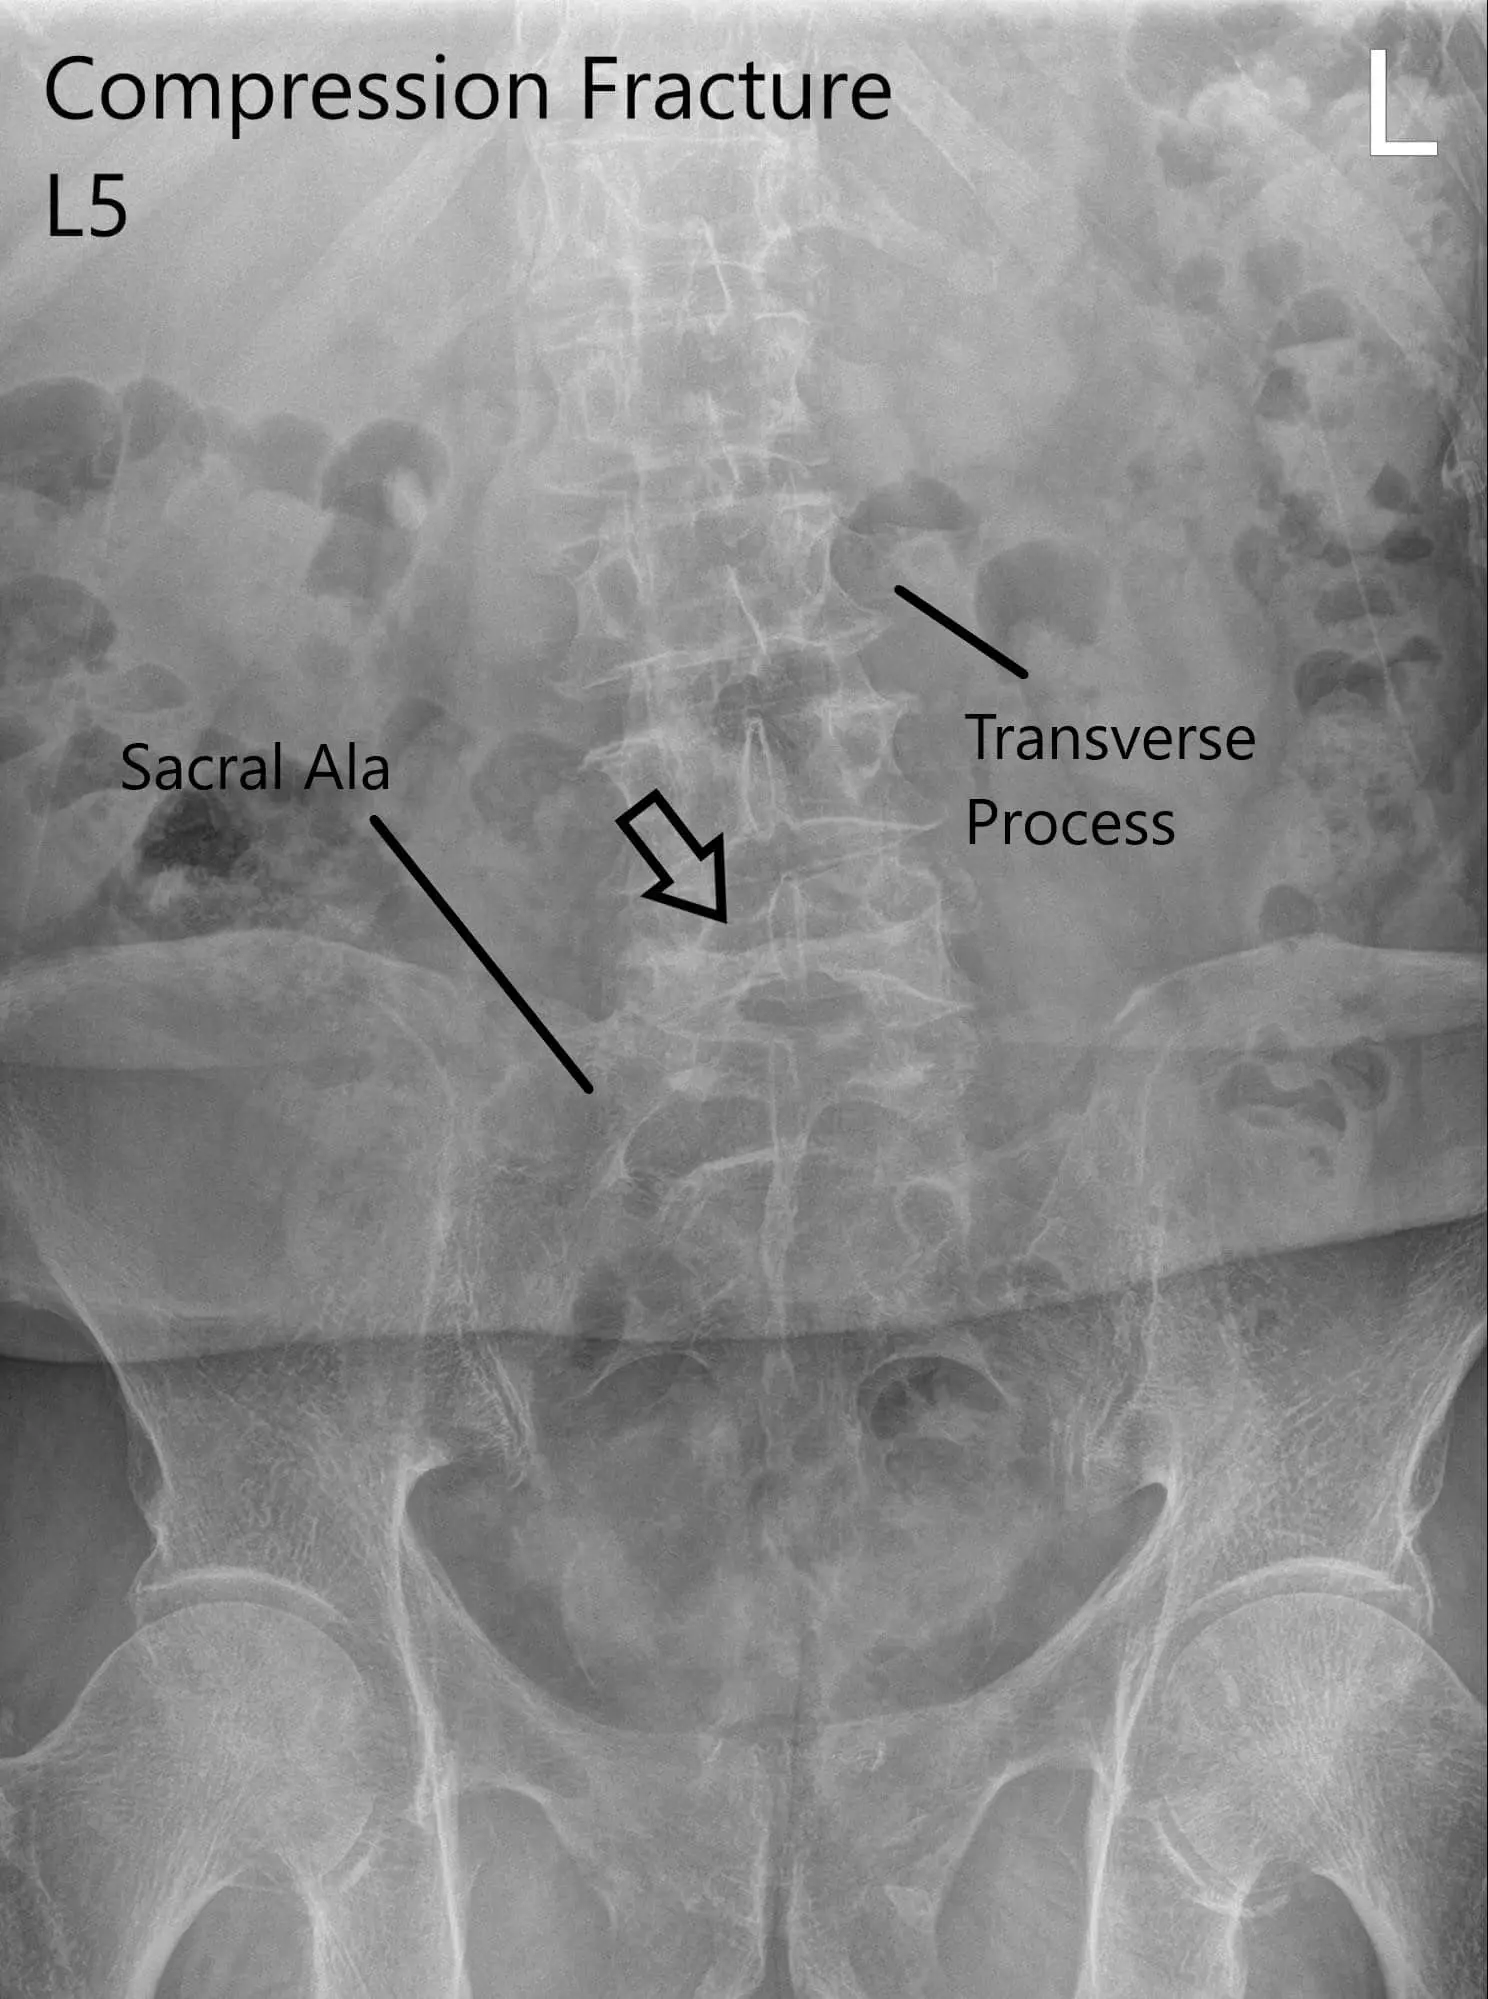

X-ray of LS spine in AP and Lateral views showing significant compression fracture L5.

The patient is in remission from rectal cancer treated with surgery, radiotherapy, and chemotherapy. Imaging was done which showed a fracture of the L5 vertebra and severe stenosis at L3/4 and LS/S1 with severe neuro-foraminal disease and degenerative changes in the spine.

CT suggested a severe compression fracture of L5 with mild retropulsion of superior endplate. Multilevel degenerative spondylosis of the lumbar spine. Moderate to severe spinal canal stenosis at L3-L4 and L4-L5 levels.